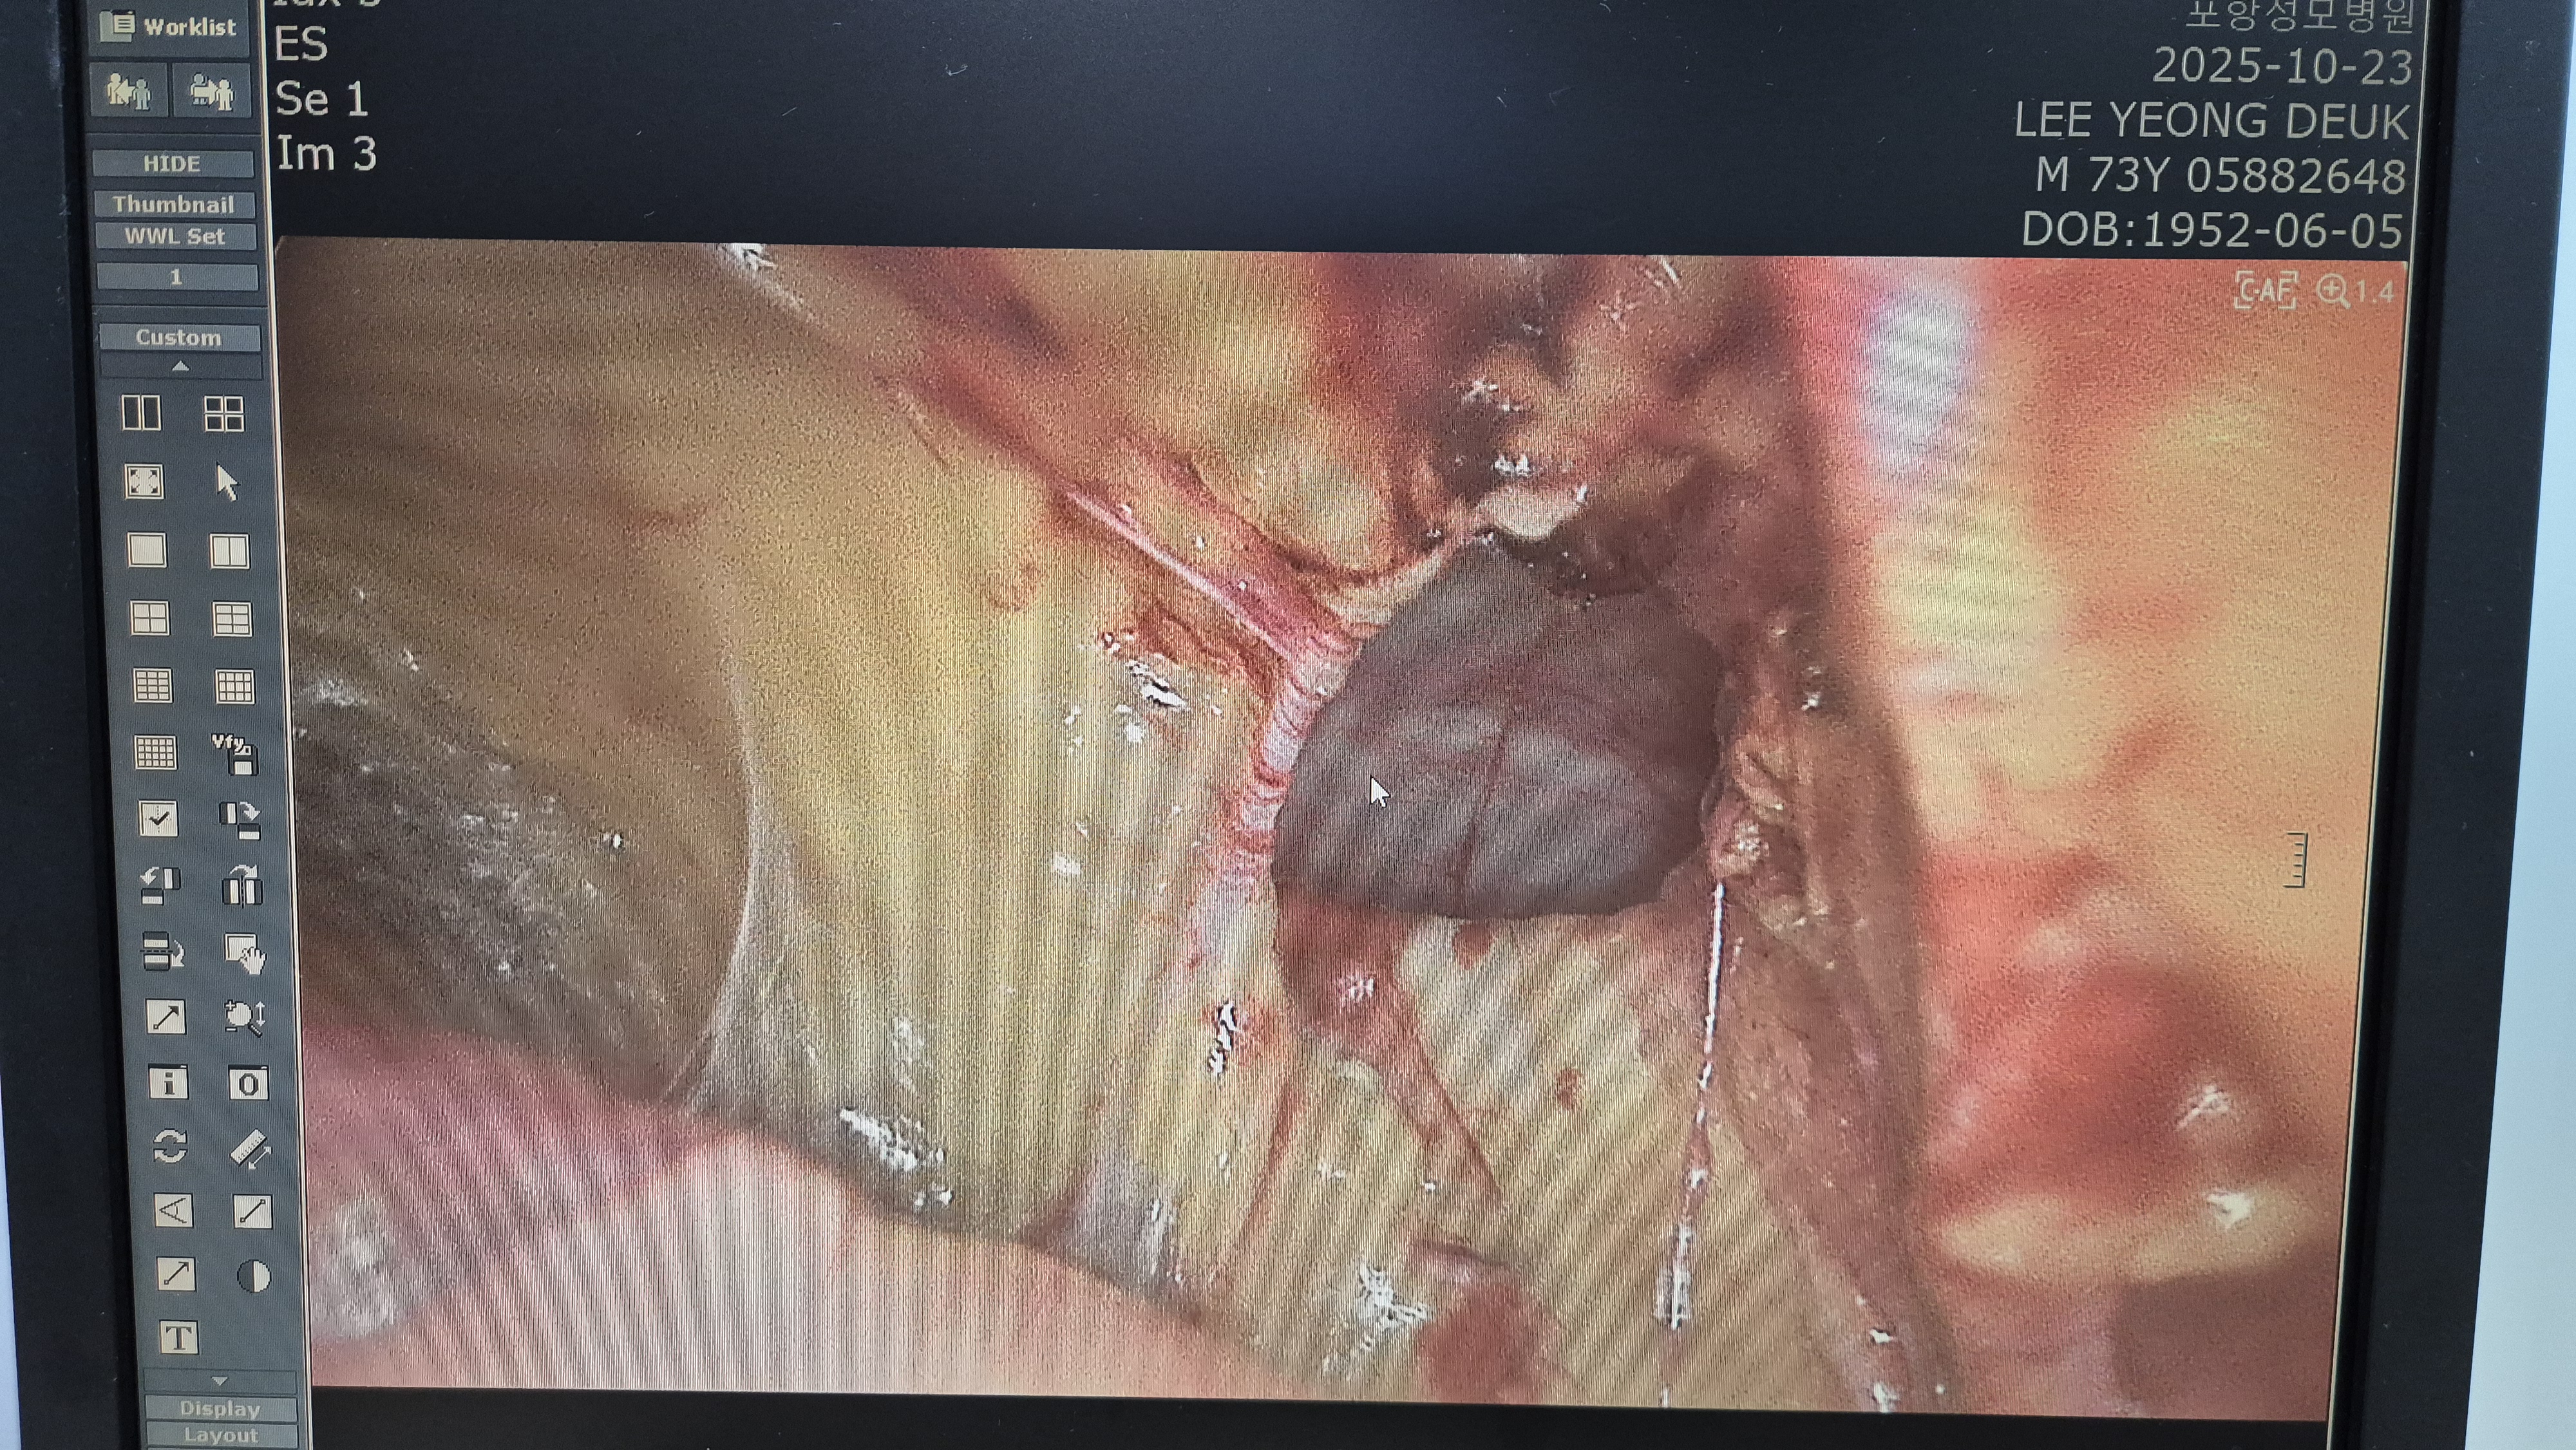

우측 직접 탈장 확인.

메쉬로 보강.